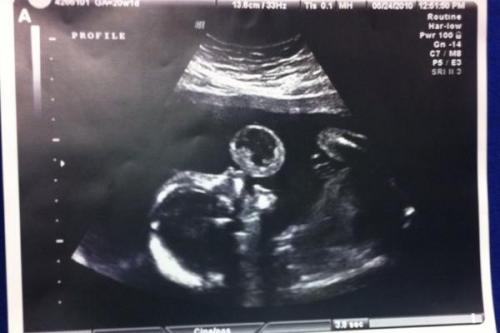

На узи видно, как малыш надувает пузырь.

Тамми гонзалес из США была на 17 неделе беременности, когда врачи обнаружили нечто необычное вовремя очередного сеанса узи. Казалось, будто малыш в утробе надувает пузырь. Увиденное, как бы там ни было, оказалось тератомой, редкой разновидностью раковой опухоли. Врачи рекомендовали тамми немедленно провести операцию по удалению образования, пока малыш еще находится в утробе. Иначе девушка могла потерять ребенка.